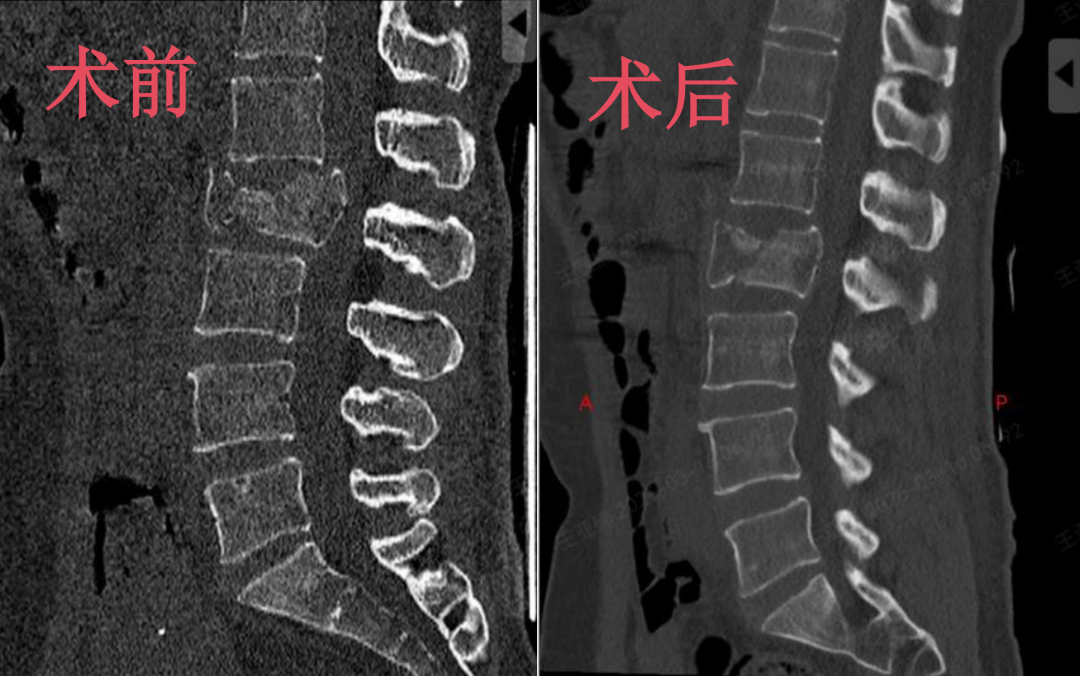

考虑到王女士年龄适中,对术后恢复速度、生活质量有着较高的需求,王肖虎主任迅速展开综合评估,结合患者病情与康复期待,为其定制了骨科手术机器人辅助下腰2椎体骨折经皮微创椎弓根螺钉内固定术的个性化治疗方案。

术后复查显示,患者脊柱稳定性成功重建,椎体高度恢复,椎管内侵犯骨块也实现精准复位。